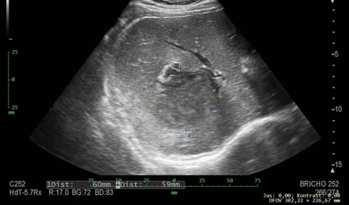

Muž, 33 let, postgraduální student z Indie, přichází na gastroenterologickou ambulanci pro nespecifické dyspeptické obtíže, febrilie a tlaky v epigastriu. Pacient udává, že je z výškové oblasti Indie a přisuzuje obtíže změně nadmořské výšky. Klinicky je nález na břiše minimální. Laboratorně jsou ale zjištěny vysoké zánětlivé parametry, elevace bilirubinu na 50 mmol/l a mírná hepatopatie. Pacient je přijat na gastroenterologické oddělení pro podezření na cholangitidu a je proveden UZ břicha, kde je zjištěn suspektní absces jater velikosti 6 × 6cm (obr. 1).

Obr. . UZ b icha s nálezem abscesového ložiska. (Zdroj: Gastroenterologické odd lení Nemocnice eské Bud jovice, a.s.)

Fig. . Abdominal ultrasound with finding of abscess deposit. (Source: Gastroenterology Department of the Hospital eské Bud jovice, a.s.)